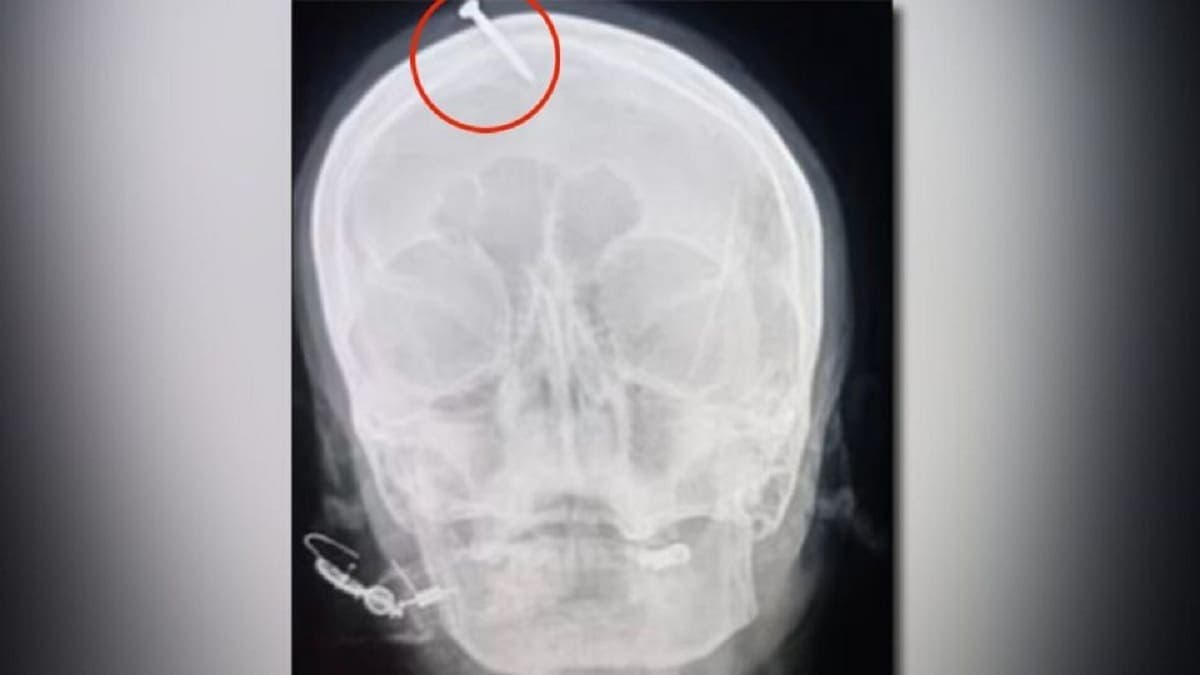

Una mujer embarazada llegó a un hospital de Pakistán con un clavo de cinco centímetros incrustado en su frente.